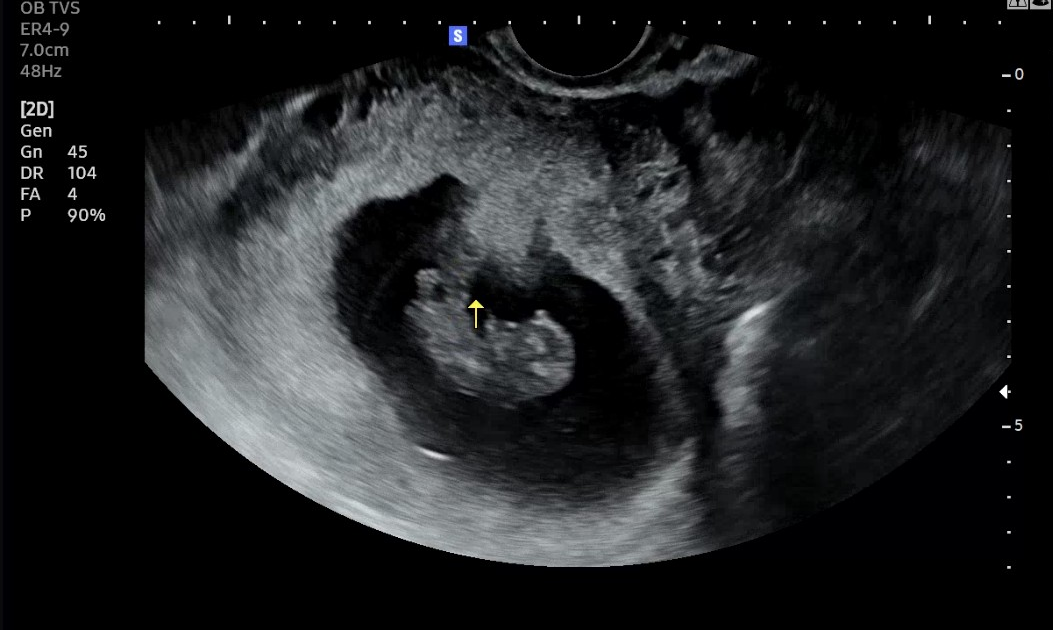

긴 대기끝에 이름이 불리고 초음파 화면이 켜졌다.

아기가 꿈질꿈질 움직이고 있었다.

생각보다 또렷했고, 생각보다 사람같았다.

개념으로만 존재하던 아기가 눈 앞에서 움직이는데

이상하게 말이 나오지 않았다.

그제야 임산부라는 말을 조심스럽게 받아들일 수 있었다.